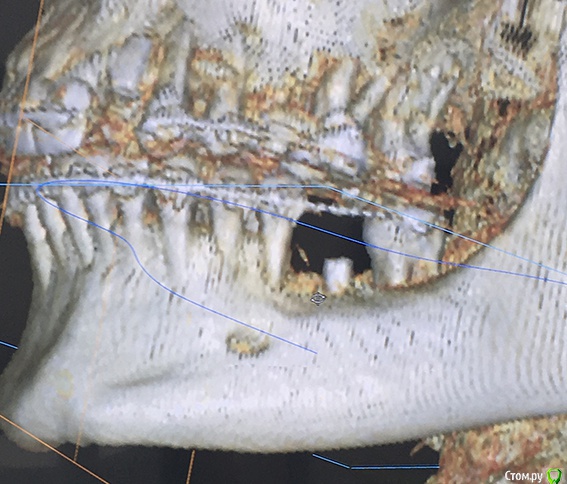

Naminutku Опубликовано 22 марта, 2019 Поделиться Опубликовано 22 марта, 2019 Уважаемые форумчане, прошу вашей помощи в сложившейся ситуации.Сразу отмечу, что нет цели кого-то уличить в непрофессиональности, есть цель разобраться в ситуации и принять правильное решение относительно дальнейшего лечения. Установлено 2 имплантата АльфаБио 3,3х8мм. Один в районе жевательного зуба, второй в зоне резца.По ряду обстоятельств после имплантации я обратилась в другую клинику за консультацией (в обеих клиниках причин сомневаться в профессионализме и добрых намерениях у меня нет)Во время консультации был сделан 3D снимок, на котором видно, что имплантат в районе жевательного зуба не полностью погружен в костную ткань и расположен на 2мм выше края кости. В районе резца имплантат выходит за пределы костной ткани (см. снимки)Врач считает, что в обоих случаях имплантаты установлены некорректно. В районе жевательного зуба в последующем мягкие ткани разрушатся и выступающая часть имплантата будет торчать, а в районе резца очень высока вероятность развития воспаления и разрушения костной ткани, + из-за особенностей позиционирования, коронку придется делать со смещением (т.е. центральные оси коронки и имплантата не будут совпадать), что вместе приведет к недолговечности всей этой истории. Предложения 2:1. оставить как есть, закончить лечение и решать проблемы по мере возникновения.2. пока имплантаты не успели намертво врасти в кость (срок чуть больше месяца), убрать, восстановиться и поставить новые имплантаты.Мне очень важно мнение профессионалов в данной ситуации. Насколько критична ситуация, стоит ли удалять, заново имплантировать или проблемы с существующими имплантатами нет? Ссылка на комментарий

red_butler Опубликовано 22 марта, 2019 Поделиться Опубликовано 22 марта, 2019 Ничего критичного я на снимках не увидел... Ссылка на комментарий

koreandr Опубликовано 22 марта, 2019 Поделиться Опубликовано 22 марта, 2019 Тоже ничего критичного не вижу Ссылка на комментарий

suballex Опубликовано 25 марта, 2019 Поделиться Опубликовано 25 марта, 2019 Плюсую. На данный момент, критических изменений нет. Ссылка на комментарий